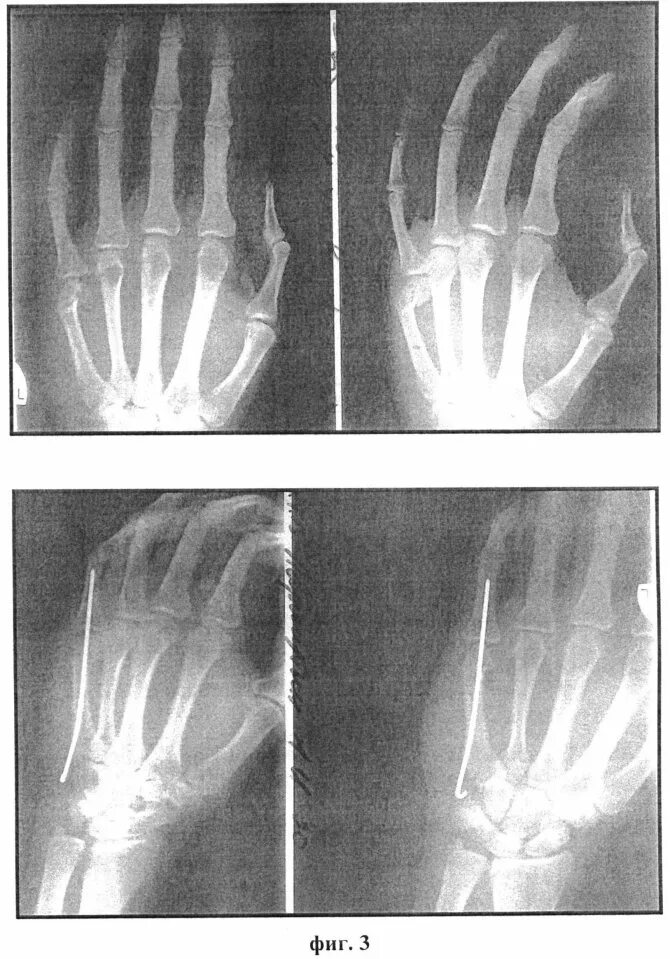

Перелом ладьевидной кости остеосинтез. остеосинтез пястной кости спицами. перелом 1 пястной кости остеосинтез спицами. остеосинтез ладьевидной кости кисти.

Перелом ладьевидной кости остеосинтез. остеосинтез пястной кости спицами. остеосинтез ладьевидной кости спицами. остеосинтез при переломе ладьевидной кости кисти.

Ладьевидная кость руки перелом. ладьевидная кость кисти костная киста. ладьевидная кость кисти перелом гипс. перелом ладьевидной кости иммобилизация.

Ладьевидная кость кисти перелом. ладьевидная кость руки перелом. перелом ладьевидной кости операция. остеосинтез ладьевидной кости кисти.